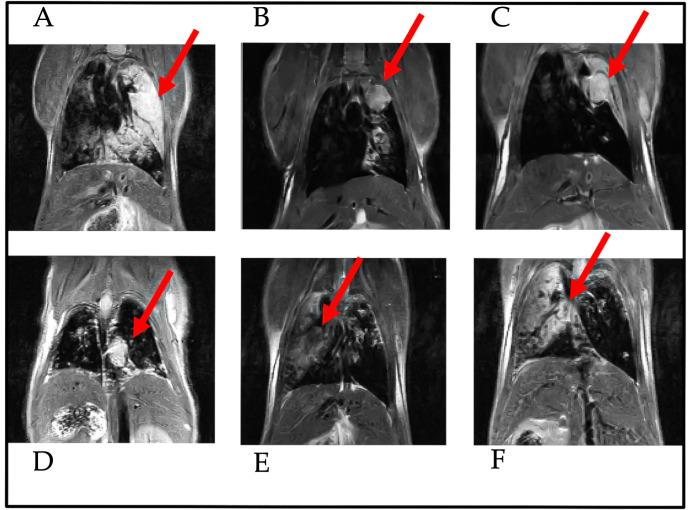

KRAS and KRAS-LKB1 conditional transgenic animal models were bred and genotyped. The tumors were inducted using adeno-CRE-recombinase system. The mice were housed in a Digital Ventilated Cage (DVC) rack measuring the locomotor activity continuously for 24/7. The progression of the tumors was monitored with MRI. The DVC system evaluated a reduction in animal locomotion during the tumor progression.

培育KRAS和KRAS-LKB1条件性转基因动物模型并进行基因分型。使用腺病毒-CRE重组酶系统诱导肿瘤。将小鼠饲养在数字通风笼(DVC)架中,每周7天、每天24小时连续测量其运动活动。用MRI监测肿瘤进展。DVC系统评估肿瘤进展过程中动物运动的减少情况。